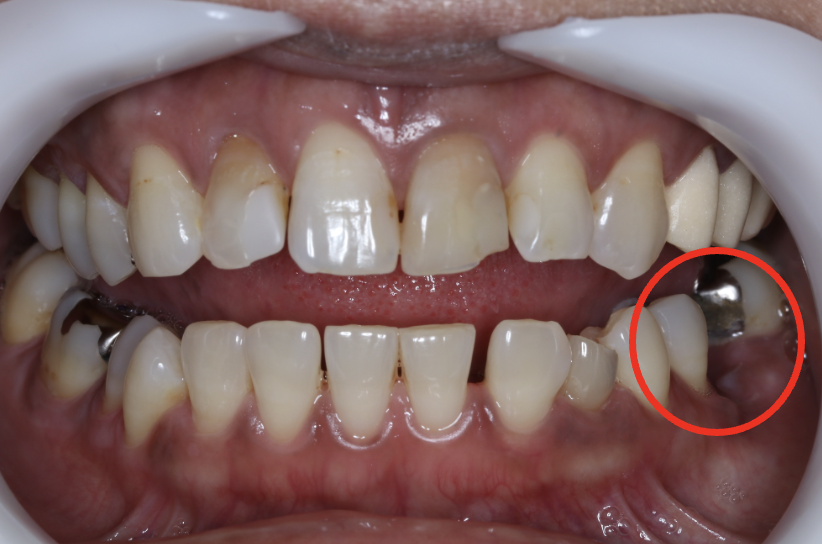

インプラント症例①

年齢 70代男性

治療期間 4ヶ月

インプラントメーカー ジンマーインプラント

治療内容 カスタムアバットメント、上部ジルコニア

治療箇所 右下5番、6番

治療費用 700,000円